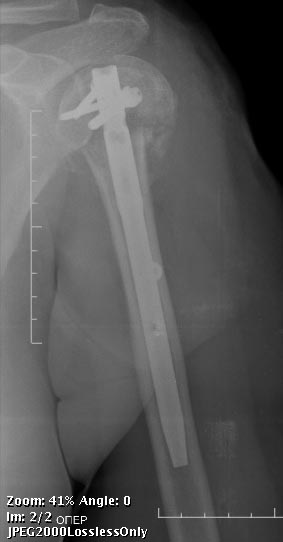

[Ortho] Перелом проксимального отдела плеча

по-другому. НаучИтесь - понравится. Вот примерчик, операция закрыто

через 2 мес. после травмы.